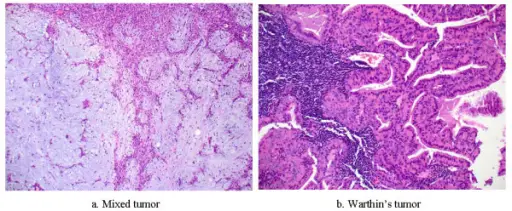

Pleomorphic Adenoma

Pleomorphic adenoma is a benign tumor made up of both epithelial and stromal tissue.

Pleomorphic adenoma is the most common salivary gland tumor.

Pleomorphic adenoma appears as a moving, painless mass that is constrained to the angle of the jaw.

Histologically pleomorphic adenomas have a myxoid component and a stromal component.

Pleomorphic adenoma is associated with the PLAG1 gene mutation.

Treatment of pleomorphic adenoma is surgical resection.

Small islands of tumor that extend through the tumor capsule frequently result in an incomplete resection.

There is a high recurrence rate for excised pleomorphic adenomas.

Rarely the benign pleomorphic adenomas may develop into their malignant counterparts carcinoma-ex pleomorphic.

Warthin Tumor

Warthin tumor is a benign cystic tumor with a stroma that resembles a lymph node and many lymphocytes.

Warthin tumor is also known as papillary cystadenoma lymphomatosum.

Warthin tumor is the second most common salivary gland tumor.

Warthin tumor occurs almost invariably in the parotid.